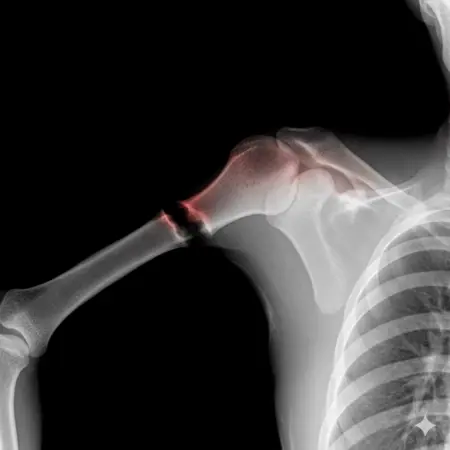

アートや写真の編集用に設計されたFlux Kontextのようなモデルを、医療画像、たとえば「単純な」骨折の赤色マーキングに使用できるか?

即答:面白い結果を出すが、過剰に反応し、医療ツールとしては信頼性に欠ける。これはアイデアを試すためのプロトタイプに過ぎない。

テスト結果:

- 偽陽性 ≈ 24%

- 骨折検出 ≈ 20%

感度モード(検出を優先、ノイズ多め)

- Euler、15ステップ、Karras

- Denoise:1.0

結果:

- 偽陽性 ≈ 80%

- 骨折検出 ≈ 86%

さらに攻撃的な設定(例:rk beta57、Denoise 1.0)では、**偽陽性100%、検出100%**という馬鹿げた結果に:すべてを赤で塗りつぶし、健常部もほぼすべて骨折と誤認する。未経験の目には区別がつかない。